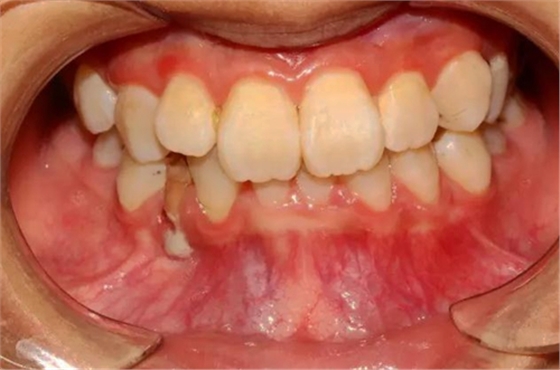

本案:患兒,女,14歲,因牙齒矯正來院,檢查見83滯留,43未見萌出,拍片發(fā)現(xiàn):43埋伏阻生于31、41、42根尖下方,按照正畸診療計劃,擬行43拔除術。

口腔牙列照片